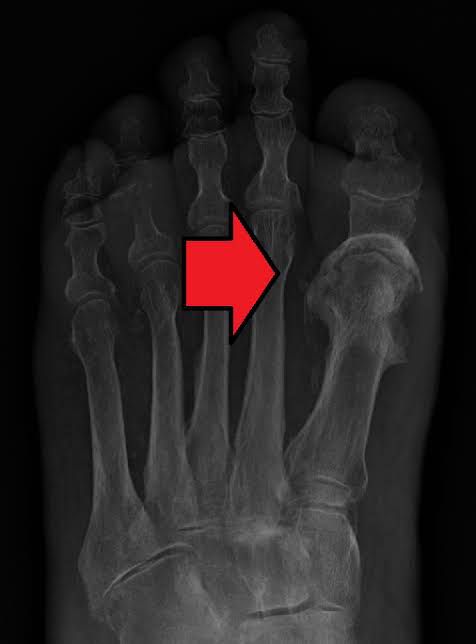

Osteomyelitis is inflammation or swelling that occurs in the bone. It can result from an infection somewhere else in the body that has spread to the bone, or it can start in the bone — often as a result of an injury. Osteomyelitis is more common in younger children (five and under) but can happen at any age.